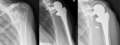

- Différentes lésion labrales post.jpg Alexandre.laedermann

19:53, 26 January 2020

1,918 × 454; 739 KB